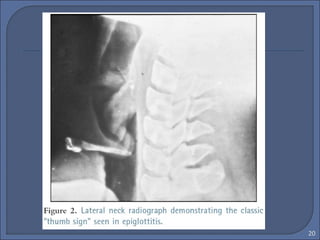

• Laringotracheitis :“ The Steeple

Sign”

• Epiglottitis : “ Thumb Sign”

 CXR : Plain film of the neck

• Steeple sign

• Overdistended hypo pharynx( lateral)